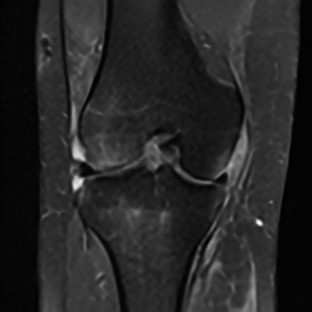

Limited by imaging systems, the reconstruction of Magnetic Resonance Imaging (MRI) images from partial measurement is essential to medical imaging research. Benefiting from the diverse and complementary information of multi-contrast MR images in different imaging modalities, multi-contrast Super-Resolution (SR) reconstruction is promising to yield SR images with higher quality. In the medical scenario, to fully visualize the lesion, radiologists are accustomed to zooming the MR images at arbitrary scales rather than using a fixed scale, as used by most MRI SR methods. In addition, existing multi-contrast MRI SR methods often require a fixed resolution for the reference image, which makes acquiring reference images difficult and imposes limitations on arbitrary scale SR tasks. To address these issues, we proposed an implicit neural representations based dual-arbitrary multi-contrast MRI super-resolution method, called Dual-ArbNet. First, we decouple the resolution of the target and reference images by a feature encoder, enabling the network to input target and reference images at arbitrary scales. Then, an implicit fusion decoder fuses the multi-contrast features and uses an Implicit Decoding Function~(IDF) to obtain the final MRI SR results. Furthermore, we introduce a curriculum learning strategy to train our network, which improves the generalization and performance of our Dual-ArbNet. Extensive experiments in two public MRI datasets demonstrate that our method outperforms state-of-the-art approaches under different scale factors and has great potential in clinical practice.